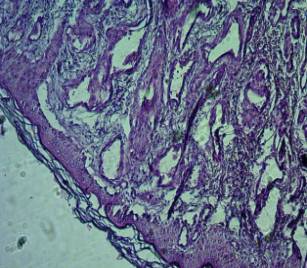

см). При микроскопическом

исследовании: в

верхней и нижней долях правого легкого, определяются множественные

капиллярно-кавернозные ангиоэктазии, представленные сосудистыми полостями,

различной величины и формы, выстланные

одним слоем уплощенных эндотелиальных клеток и разделены

соединительнотканными прослойками различной величины (Рис.1). В просвете

полостей эритроциты. На остальном

протяжении морфологическая структура ткани не нарушена.

Рис.1

Капиллярно-кавернозные ангиоэктазии в правом легком.

Гистопатологическое

исследование кожного лоскута с правого

предплечья - субэпителиально

определяются множественные капиллярно-кавернозные ангиоэктазии сосудистыми полостями, различной величины и формы,

выстланные одним слоем уплощенных

эндотелиальных клеток (Рис.2).

Рис.2

Капиллярно-кавернозные ангиоэктазии в коже правого предплечья